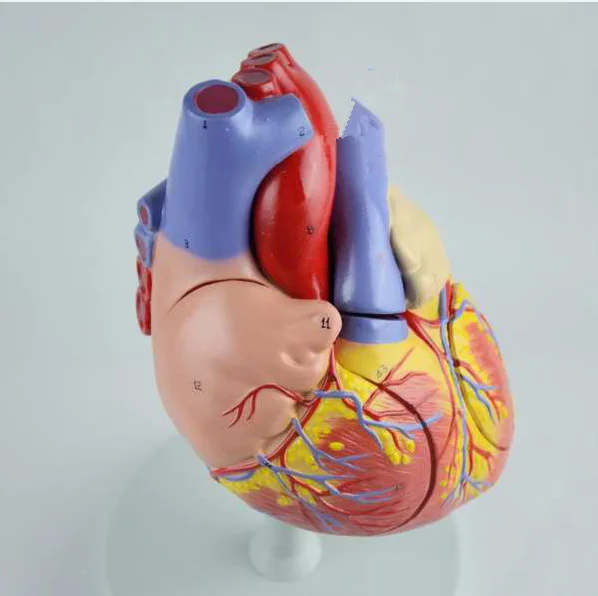

Фотографии и 3D-модели анатомии сердца человека